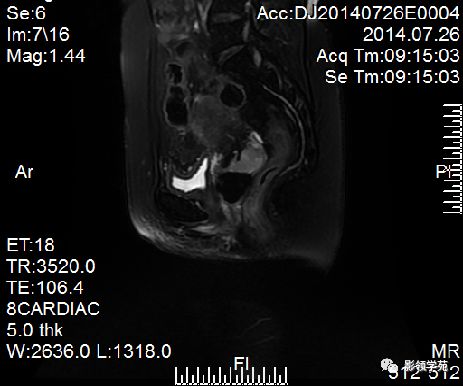

- 扫描序列:SAG T2WI,AXI T1WI+T2WI, COR T2WI 。其中SAG T2WI最重要

宫颈癌可表现为类圆形或不规则形肿块,在T2WI上表现为均匀或欠均匀的高信号,与正常宫颈基质及宫旁脂肪形成良好的自然对比。

- Ⅰ期肿瘤:侵犯宫颈基质,T2WI等信号肿块,宫颈管扩大及宫颈纤维基质中断

- Ⅱ期肿瘤:宫颈增大,宫旁肿块或宫旁脂肪组织内出现异常信号的粗线状影

- Ⅲ期肿瘤:侵犯至阴道下部,外延至盆壁,或出现肾积水。

- Ⅳ期肿瘤:膀胱壁或直肠壁低信号中断,膀胱壁或直肠壁增厚或腔内肿块。